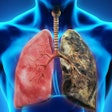

Two drug-sensitive cases (above) and two drug-resistant cases (below). Each column shows one x-ray image and one CT slice. Images courtesy of Vasiliy Kovalev.Feature analysis

Can radiologists see signs of drug resistance by patterns in the lung parenchyma?

Some manifestation of the differences between drug-sensitive and drug-resistant cases in the lung parenchyma and lesion structure may be visible, Kovalev wrote. But a deeper multidisciplinary study of resistance will still be necessary to identify and isolate any signs in radiologic images.

Even so, "my experience suggests that it is often the case in biomedical image analysis studies that computerized features and radiological (human) visual features could be very different," Kovalev wrote.

Doctors can be excellent at detecting lesions, calcifications, etc., but diseases can manifest nonlocally -- for example, just by changing the proportions of structures occupied by light or dark pixels on an image. What humans can't see, computers often can, Kovalev wrote.